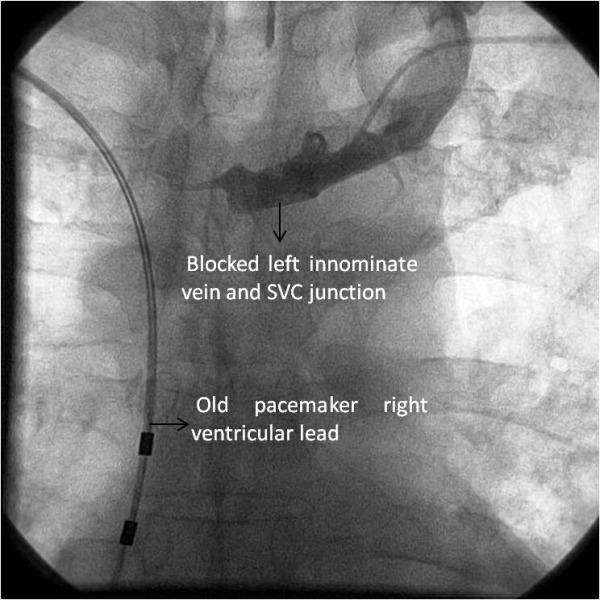

Percutaneous transvenous angioplasty of left innominate vein stenosis following right side permanent pacemaker implantation- a left femoral vein to left axillary vein approach.

Central venous stenosis after the insertion of a permanent pacemaker is a well recognized complication. This late complication is encountered when there is a need to change the pacemaker lead or extract it. We describe a young male who had such a complication after many years after right side pacemaker implantation. The lesion was managed percutaneously leading to placement of a new lead from the left side.